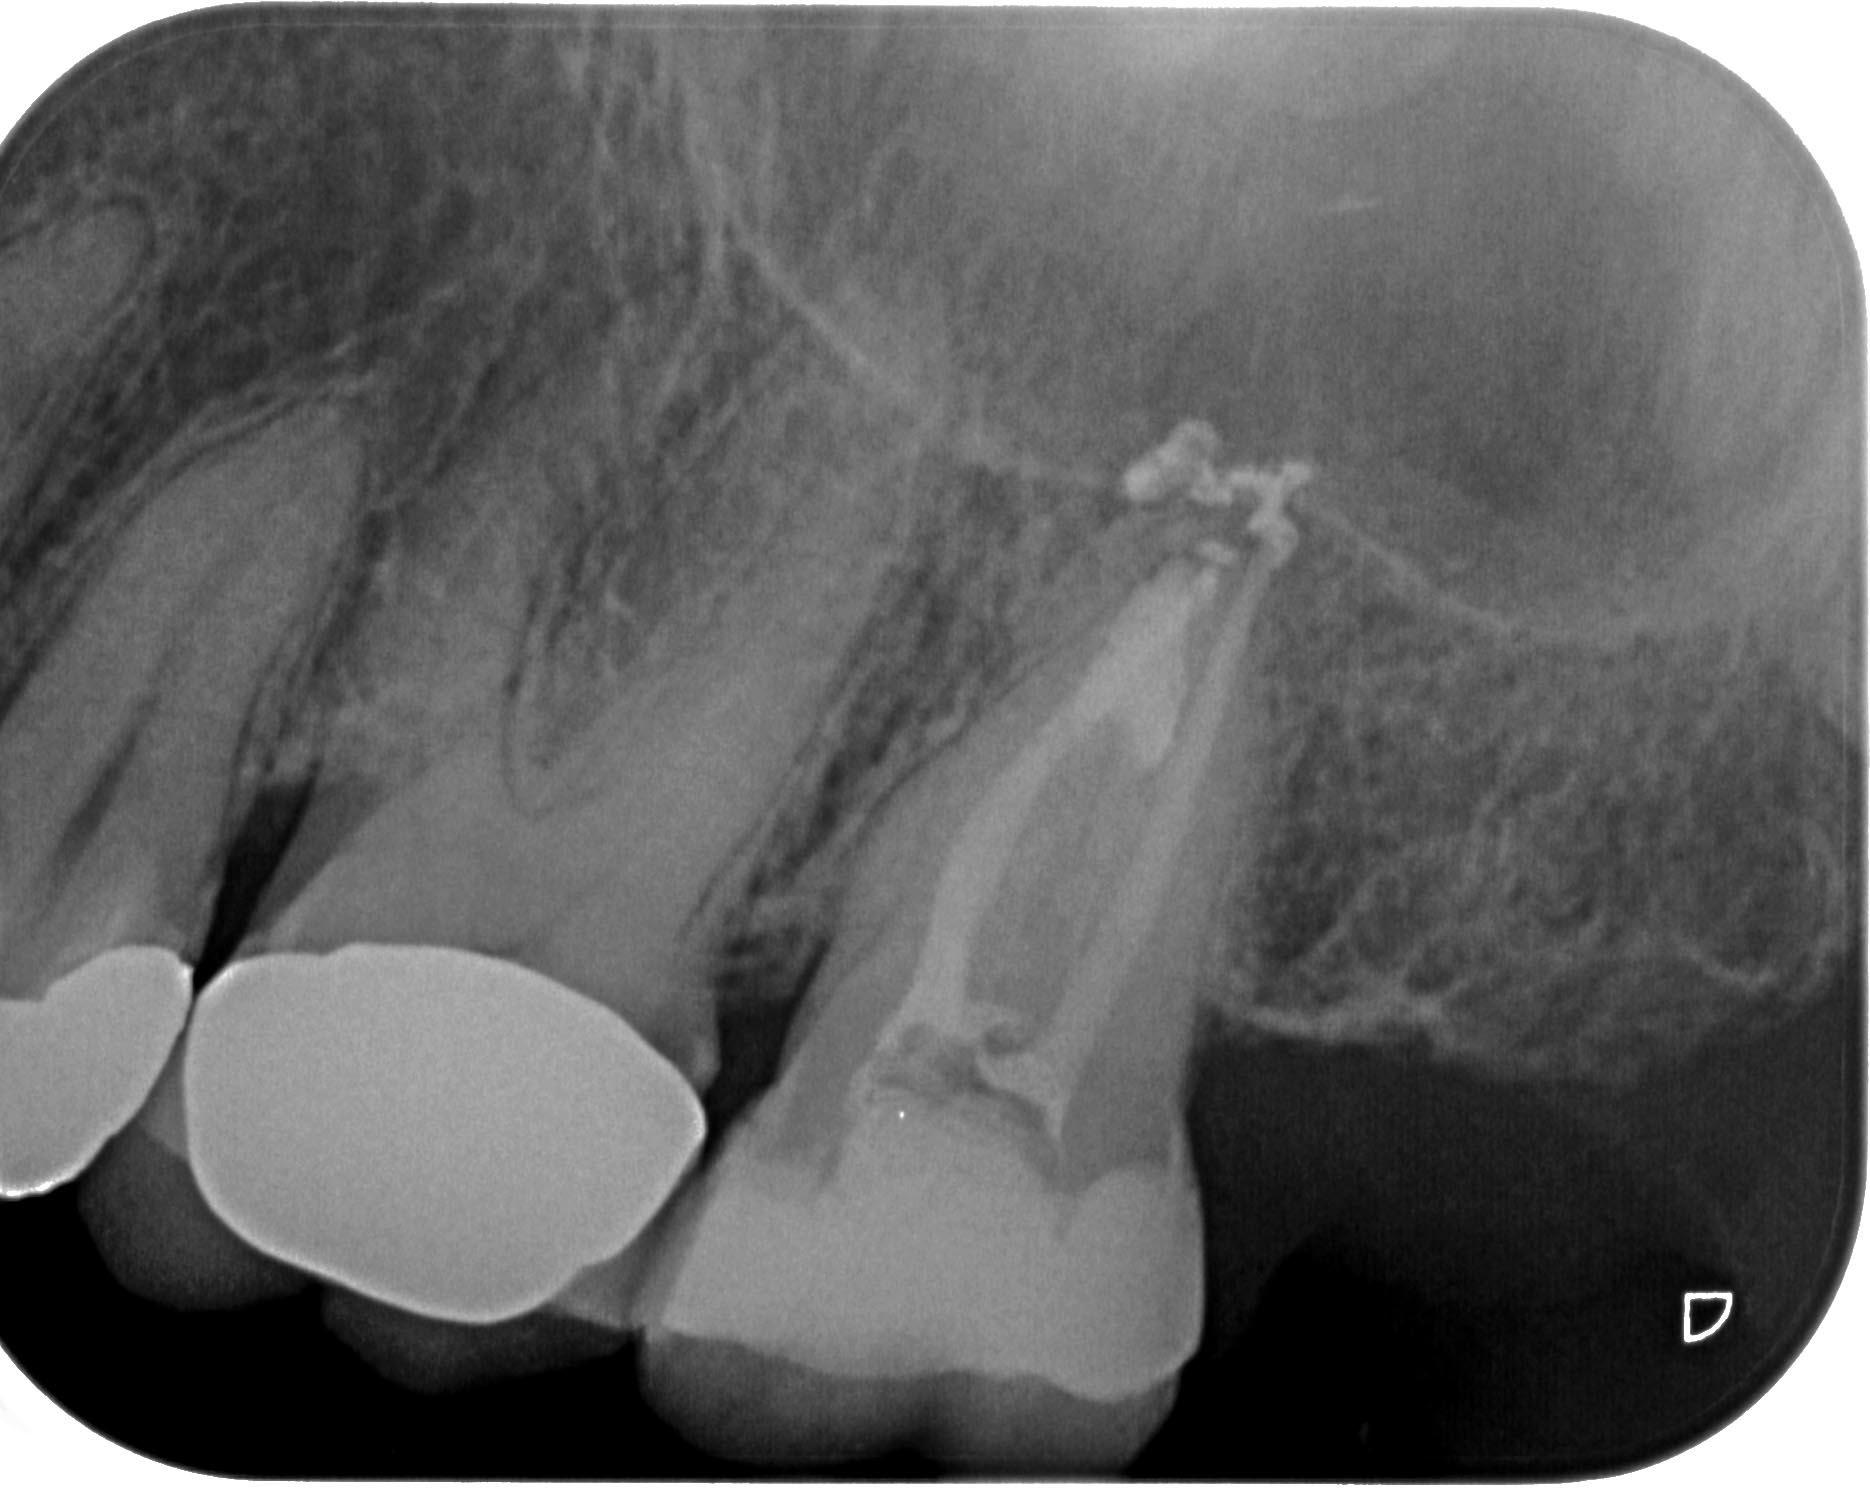

KC27-1-5 Veröffentlicht 25. Juni 2015 am 1870 × 1491 in Zahn 27- Interne Resorption, apikale Aufhellung